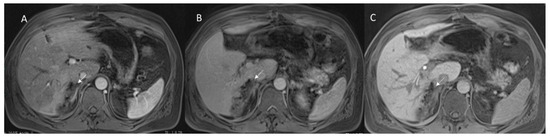

3.1.4. Biliary Injuries

3.2. Late Postoperative Complications

3.2.2. Late Strictures and Ischemic Cholangitis